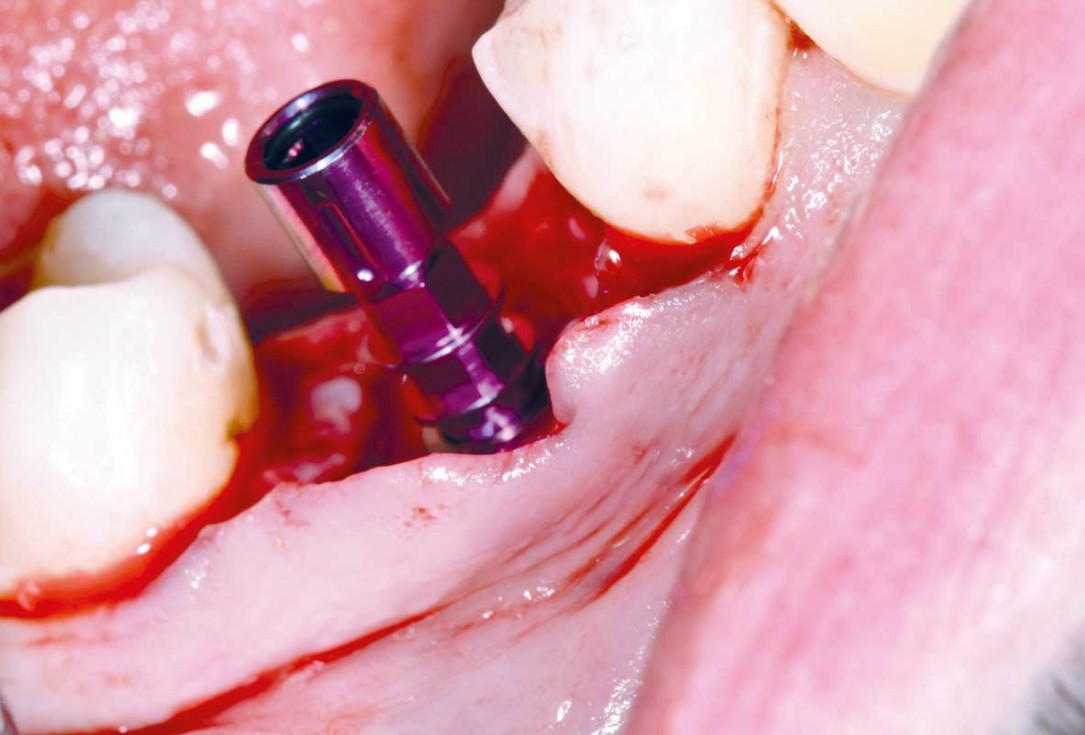

03/25 - Situation after tooth extraction and implant placementImmediate implant placement and peri-implant bone augmentation with cerabone® plus - Dr. R. Block Veras